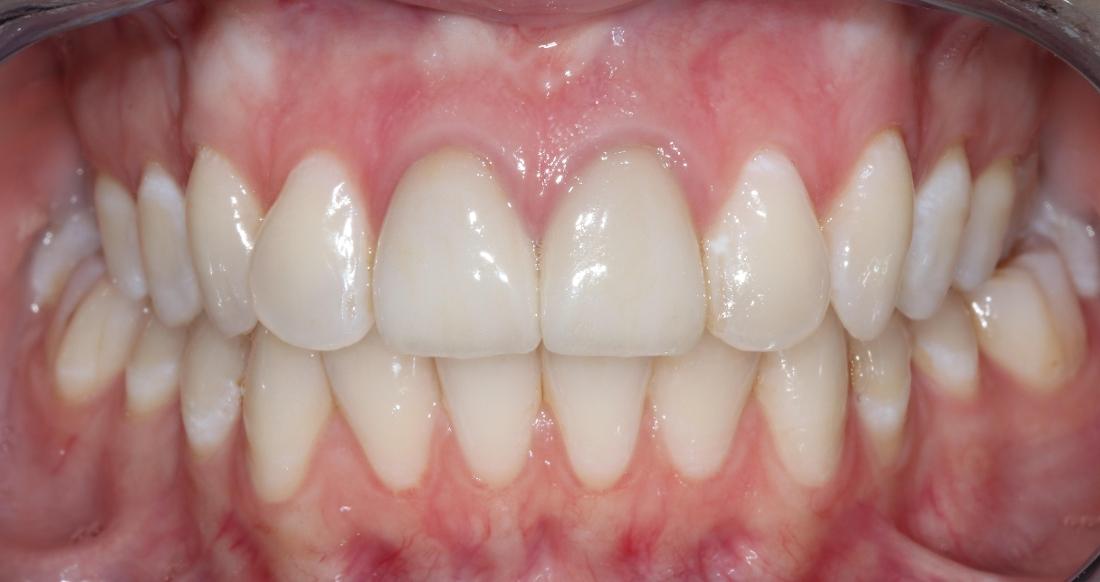

This dental patient arrived at our dental office in Goffstown requesting a straighter smile. We knew this patient would be a perfect candidate for Invisalign clear aligner treatment. After a short consultation, our expert dental team got to work on the Invisalign process and in a few short months, this patient was able to smile with confidence.

One of the first priorities was getting my teeth straightened. I was surprised when I was offered a solution right there at my primary dentist office and did not have to travel to a specialist. I recently got my brackets removed after about a year and the results are AMAZING! The best part was the level of care I received along the way. Any time I had a question or concern it was addressed immediately and they always made time for me to stop by. They have been exceptional with the level of patient care they provide!